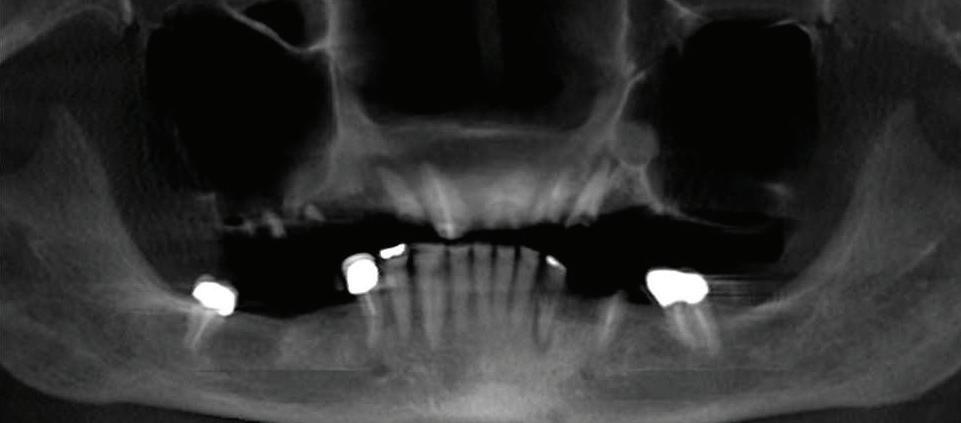

Can just four implants replace all of the teeth on the top or the bottom of your mouth? Thanks to advances in dental implant technology, that answer is a resounding yes.

Believe it or not, tooth loss is extremely common among adults, especially as we age. In fact, more than 35 million people in America are missing all of their upper and/or lower teeth. Rather than living with the discomfort and hassles of dentures, many people are opting for what is called “all-onfour” dental implant restoration.

All-On-Four: One Full Arch Of Teeth, Four Dental Implants

To fully understand this remark-

able technique for replacing teeth, you should first understand what a dental implant is. An implant is a small titanium screw that fits inside your jawbone and replaces the root-part of a missing tooth. Minor surgery is required to insert the implants. Once the implant is in place, a crown is attached to give you a highly realistic-looking and functional prosthetic tooth.

Here’s where it gets really interesting: You do not need a dental implant for each and every one of your missing teeth. All you need is four precisely placed implants on the top of your mouth, and four on the bottom, to restore your full smile. That’s the beauty of the all-on-four. And because the implant is made of titanium, it has the unique ability to fuse to living bone and function as part of it. So eventually, the dental implant becomes part of the jawbone and serves as a strong, long-lasting foundation for your new teeth.

Besides ensuring that your implants are permanently fixed in place,

Missing Teeth or Tired of Wearing Dentures?

Thanks to advances in dental implant technology, just four implants can replace all of the teeth on the top or the bottom of your mouth.

this bone fusion has another important benefit: it prevents future bone loss in the jaw. This helps to maintain a more youthful facial structure – and better oral health. But perhaps the biggest surprise about the all-on-four is how quickly it can transform your life.

What’s The All-On-Four Dental Implant Procedure Like?

It can be scary to get implants for the first time. Most of that fear is probably due to the uncertainty, so here is the step-by-step process for getting an All-On-Four dental implant.

First, your dentist will want to make sure your comfortable, so either local or general anesthesia will be administered.

Second, the dentist or surgeon will prepare your mouth for the implants, which involves removing your remaining teeth that are failing. They will then remove any diseased or infected tissue from your jaw and gums.

Next, they will begin the implantation process. This means they will

insert the titanium screws into your jawbone. Most likely, they will place two implants toward the front of your mouth and two towards the back of your mouth so the “anchors” can evenly bare the force of the denture.

After the implants have been placed, they will thoroughly clean the surgical sites and suturing all the incisions. Then you’ll be taken to a recovery room where you can relax and take time to wake up from the anesthesia.

How Do You Know If The All-On-Four Procedure Is The Right Option For You?

At your All-On-Four consultation, you’ll receive a 3D CT Scan. This scan will help determine if you need implants and assist your doctors in creating your treatment plan. So if you want to learn more about dental implants, simply schedule a consultation with an All-On-Four provider. It’s the best way to find out how dental implants can change your life.